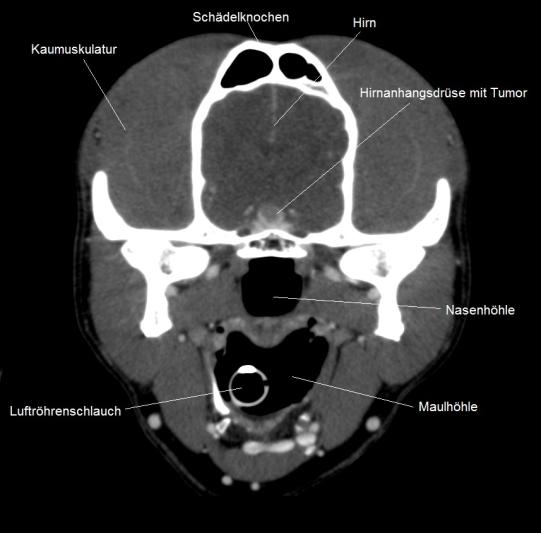

Weitere Blutuntersuchungen am Unispital unterstützen den Verdacht eines hypophysären Cushingsyndroms; ein abschliessendes Computertomogramm bestätigt dann, dass sich in der Hirnanhangsdrüse ein kleiner Geschwulst gebildet hat, welcher offensichtlich hormonell aktiv ist.

Computertomogramm des Kopfes (Querschnitt) - Bildmaterial: Tierspital Zürich, Abteilung für Bildgebende Diagnostik und Abteilung Radio-Onkologie